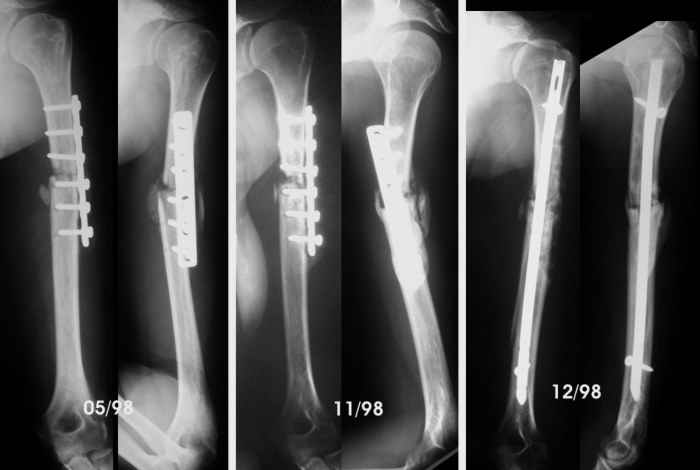

By the end of May, she complained of sudden pain during physiotherapy, and came with the bottom left x-Ray. We advised to revise the operation, but she wanted to wait in a brace, but by November the humerus hadn't healed so we advised to remove the plate, add more bone graft and nail it. Which we did.

The patient regained full motion and used the arm almost freely till now. She has been working as waitress, postman... although the x-ray never showed healing. She has never wanted to be operated again because the limb was almost pain free.